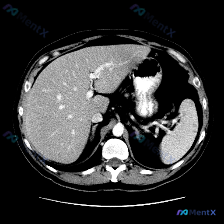

最近看到一份有意思的影像资料,不是因为发现了典型病变,而是恰恰相反——预设了“脾脏病变”的问题,但图像里却找不到明确异常。整理一下思路分享给大家。 --- 一、先看影像信息(单帧上腹部CT软组织窗横断面) 直接说客观看到的: 1. 肝脏:轮廓尚平滑,肝叶比例正常,实质密度大致均匀,肝内血管走形正常,...

看到一个很有意思的“预设型”病例,整理一下思路和大家分享。 临床背景与影像资料 这次的情况有点特别:临床提示关注“脾脏病变”,但提供的是一张单张的腹部CT横断面软组织窗图像。 先说说图像里能看到的: - 肝脏:实质密度均匀,无局灶性占位,边缘光滑,肝叶比例正常; - 脾脏:位于左侧,形态、大小在本断...

整理了一份挺有意思的影像读片案例,核心不是“是什么病变”,而是“如何面对前提与证据的冲突”。 影像资料基础 - 检查方式:上腹部增强CT(横断面,软组织窗) - 图像质量:清晰,无明显伪影,对比剂充盈良好 - 显示范围:上腹部层面,包含肝脏、胃、脾脏、腹主动脉及部分腰椎 客观影像表现 1. 肝脏:形...

今天看到一个很有意思的影像案例,用户一开始就预设了「脾脏病变」的存在,但当我仔细看完这张单层面的上腹部CT平扫后,发现结论可能和预设不太一样。整理一下思路和大家分享。 --- 先看影像基础信息 这是一张上腹部CT横断面软组织窗图像,层面清晰,软组织对比度良好,没有明显运动或金属伪影。能看到肝脏、胃、...